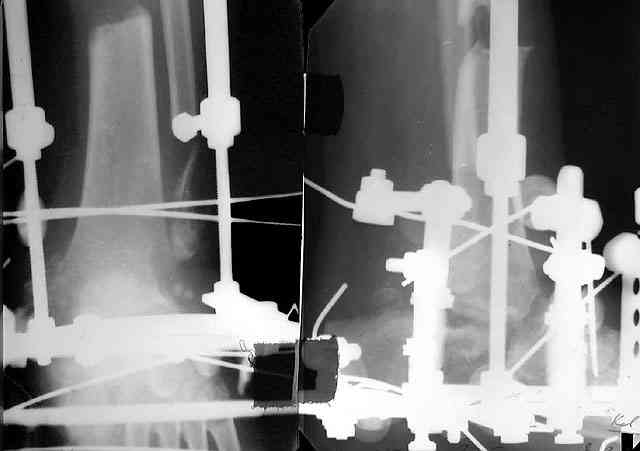

Не адресована другая проблемы - берцово-пяточный блок достигается ценой укорочения конечности на 3-4 см. Поэтому надо предусмотреть что-то для удлинения. У нас в клинике традиционный подход - билокально удлинять большеберцовую кость. Раньше еще и малоберцовую рубили на двух уровнях. Сейчас (спасибо коллегам из форума) пользуемся только

той остеотомией, которая делается для отворачивания кожно-костного лоскута с малоберцовой костью. Фиксируем все это аппаратом (пример в приложении) около 4 мес.

То есть относительно недолго. Про винты поэтому стоит вспомнить, только если опору со стопы хочется снять совсем уж рано. Можно, в принципе, и о штифтовании подумать. Правда, мы пока думаем - они так срастись успевают.